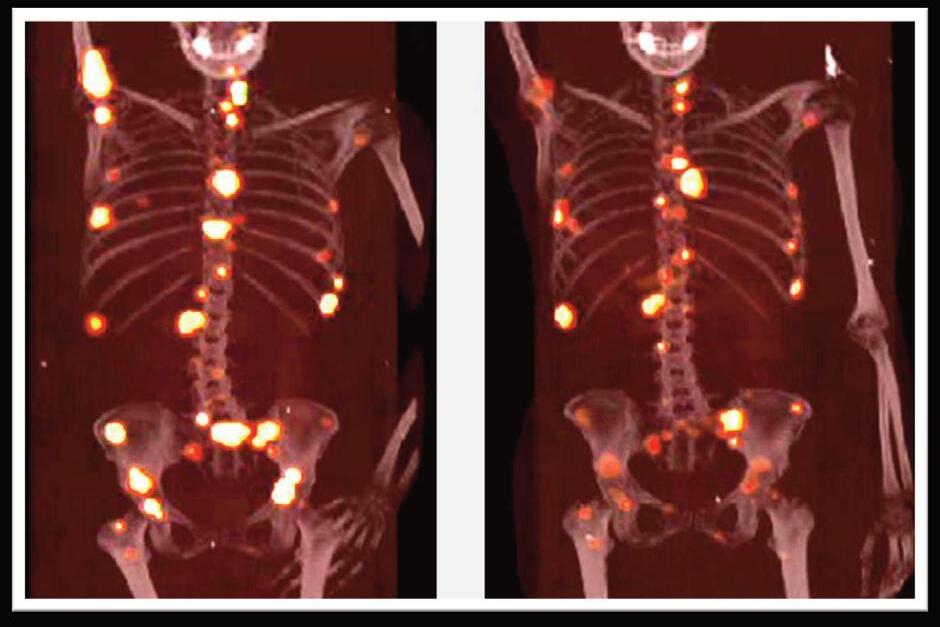

Massimo Salvatori, Francesco Bertagna, Alfredo Campennì, Francesca Capoccetti, Arnoldo Piccardo